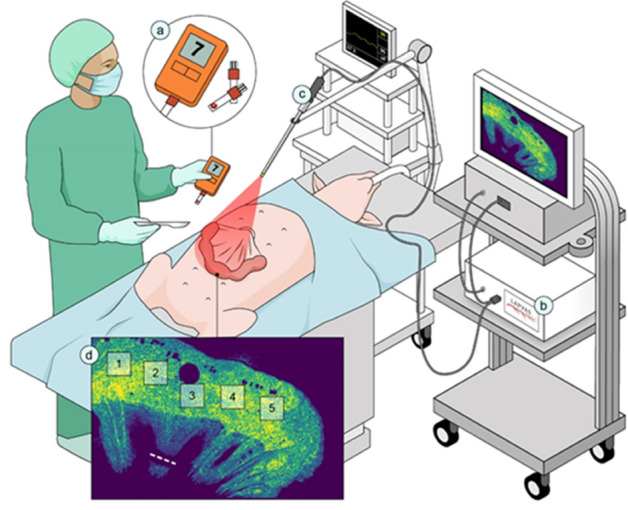

Introduction: Real-time physiologic imaging is an inevitable necessity to improve clinical outcomes. Today, indocyanine green (ICG) is commonly used for intraoperative assessment of tissue perfusion, however, its use is complicated by: (1) pharmacokinetics and user interpretation variance; (2) workflow inconvenience; and (3) capital costs. Laser speckle contrast imaging (LSCI) uses coherent laser light to show perfusion in open surgery, but no form-factor exists for MIS use (laparoscopic or robot-assisted). We report an interim analysis of the first multi-center usability and utility clinical trial using a dye-less technology, and real-time relative quantification of tissue perfusion from preclinical studies.

Methods: ActivSightTM, an FDA-cleared device, consists of an imaging module (an adapter positioned between any white light camera and laparoscope) and a light engine. LSCI detects tissue perfusion without an external fluorophore and displays it to the surgeon as a color heatmap. ActivSightTM also visualizes ICG using near infrared fluorescence (NIRF). Usability was determined using human factor testing on a Likert scale (1–5) while utility was measured by comparing perfusion detection between ICG and LSCI modes (without fluorophore). Accuracy of ICG and LSCI perfusion display was determined in user post-hoc survey comparing white light, ICG, and LSCI intraoperative images from sleeve gastrectomies. Relative quantification was measured in co-axial spotlighted areas, translating a perfusion heatmap to numerical values using proprietary algorithms.

Results: 66 consecutive patients undergoing elective MIS colorectal, bariatric surgeries, and cholecystectomies (LC) (Table 1) between 11/2020 and 07/2021 were enrolled (NCT#04,633,512). Usability evaluation (n = 22 surgeons) demonstrated: display quality of 4.07 + 0.86; ease of setup 4.26 + 0.85; and form-factor 3.82 + 1.57; and weight 3.73 + 1.10. No adverse events occurred in patients, surgeons, or systems (Table 1). Perfusion boundaries (Fig. 1A–D) on post-hoc surveys (n = 10) were concordant between intraoperatively identified boundaries (ground truth) and LSCI images (p = 0.329), and significantly discordant with ICG images detected within two minutes of first ICG injection (p = 0.043). After multiple ICG injections, residual ICG was detected in non-perfused tissue (Fig. 1E). This false-positive display was absent when using LSCI (Fig. 1F). In porcine models, relative perfusion units obtained using LSCI (Fig. 1I–L) were significantly higher in vascular vs non-vascular tissue (294.41 vs 35.08, p < 0.0001).

Conclusion: Combining LSCI and NIRF in a laparoscopy-compatible form-factor, ActivSightTM, provides accurate, repeatable, on-demand, real-time visualization of tissue perfusion without a fluorophore. Perfusion detection and display using LSCI showed more spatiotemporal accuracy than ICG. The preclinical quantification feature of ActivSightTM detects and displays consistent specific perfusion measurements.